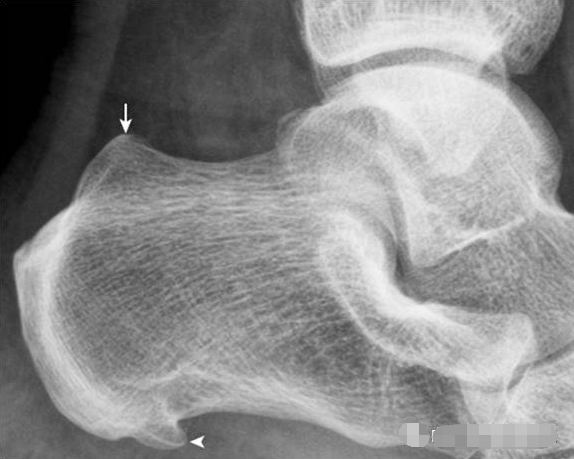

2.Haglund外生骨疣与不典型骨刺:

跟骨后上缘骨刺样突起(箭),属正常变异,称Haglund外生骨疣。穿高跟鞋时可损伤相邻的跟腱,形成Haglund综合征;跟骨结节下缘前突骨刺样突起(箭头),正常人可见,可无临床症状。